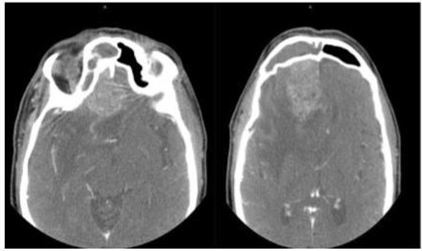

A Cerebral CT scan shows filling of the right ethmoidal cells with lysis of the middle and lower turbinates associated with complete filling of the right frontal sinus and ethmoidal enhancement. There is a heterogeneous mass strongly enhanced by the right frontal contrast medium surrounded by a halo of edema creating a mass syndrome on the medial structures with infiltration of the white matter and subfascial involvement. This image would suggest an abscess with a sinus origin, a glioma cannot be ruled out (Figure 1).

Figure 1 Cerebral CT scan with contrast injection showing the tumor associated with a large edema and midline deviation.

In our case, the brain scan was atypical. It showed the filling of the right ethmoidal cells with lysis of the middle and lower turbinates associated with complete filling of the right frontal sinus and ethmoidal enhancement. There was a heterogeneous mass strongly enhanced by contrast medium in the right frontal area surrounded by a halo of edema creating a mass syndrome on the medial structures with infiltration of the white matter and subfascial involvement. This image raised the suspicion of a sinus abscess without ruling out a glioma (Figure 1).